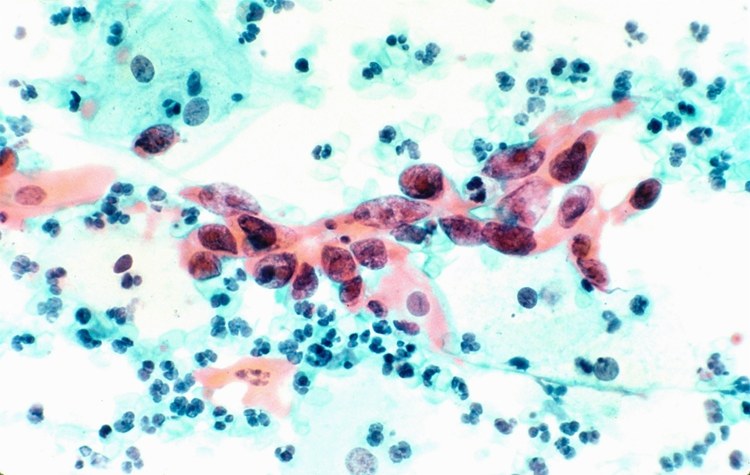

光学显微镜下的宫颈癌细胞。/ quanjing